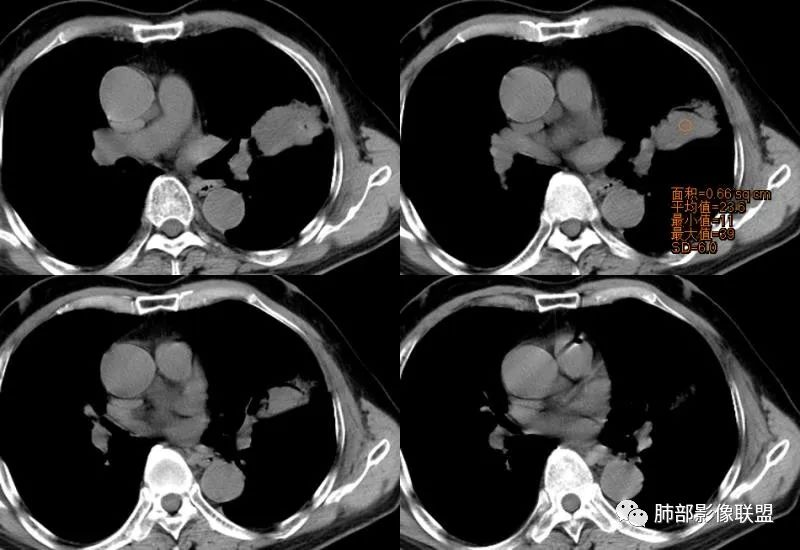

左肺上叶类圆形软组织影,边界较清楚,其内密度均匀,外侧缘可见空气新月征,并可见点状钙化,增强扫描可见均匀强化,病灶周围可见磨玻璃渗出性密度影,斜裂侧光滑平整。考虑炎性病灶,以肉芽肿性炎症为主(如真菌性肉芽肿),鉴别结核(无卫星灶,无多态性),肺癌(无毛刺,分叶等恶性征象,)细菌性炎症(密度一般不这么致密,很少钙化及空气新月征)。 医学百科网 | YxBaike.Com

胸部CT:左肺上叶类圆形肿块影,边界较清楚,密度较均匀,内可见小片坏死、偏心空洞、空气新月征、点状钙化,周围晕、絮状渗出、边缘模糊,支气管扩张、充气征、支气管进入病灶堵塞,叶裂牵拉明显,增强扫描中度均匀强化,纵隔可见淋巴结。考虑:炎性病灶,肉芽肿性炎症,曲霉?毛霉?鉴别:TB,淋巴瘤。 医学百科网 | YxBaike.Com

一米阳光:

左上肺类圆形肿块影,边界较清楚,支气管通畅略扩张,周围磨玻璃影,其内密度均匀,外侧见空气新月征,且见点状钙化。叶间裂光滑稍膨隆。老年男性,糖尿病,高血压,痰培养克雷伯菌。综合考虑炎性病灶,克雷伯合并真菌感染,曲霉。结核合并真菌。鉴别肺癌合并感染。 医学百科网 | YxBaike.Com

这个空洞的性质很重要,对最后诊断结果影响大,如果中间没有曲菌球,那就是偏心空洞,指向恶性,如果是曲菌球引起的新月形改变,那就不一定。至于到底是曲菌球还是偏心空洞,需要仔细看看强化情况。 医学百科网 | YxBaike.Com

1、团片状,实行密度区外观整体圆顿,位于上叶尖后段与下舌段区间。局部膨隆,但未见分叶,肿瘤多见。 医学百科网 | YxBaike.Com

2、偏心空腔病灶,气腔略呈新月形,壁不规则,腔内结节相对密实,明显强化且不均,支持新生物而非曲菌球等。炎性空洞多有强化环。

3、病变强化较明显,其内隐约显示多发小斑片状无强化灶,可疑边界不清小灶坏死区。病灶内血管影浅淡、模糊不规则。 医学百科网 | YxBaike.Com

4、支气管改变:上舌段支气管远段延入部分稍示僵硬。尖后段见分支支气管阻塞,恶性多见。

5、周围磨玻璃,3个月后逐渐转为密实,应符合当初附壁生长为主,且逐渐向实体成分转换。

6、病变长轴平行且受限于胸膜,外围大内带小,符合外朝内发展病变。“腔内结节状明显强化”加之支气管改变有力支持新生物诊断。如此大范围边界不清的磨玻璃影让人浮想联翩。如此大范围病灶,肺门纵隔未见肿大淋巴结也让人意外。